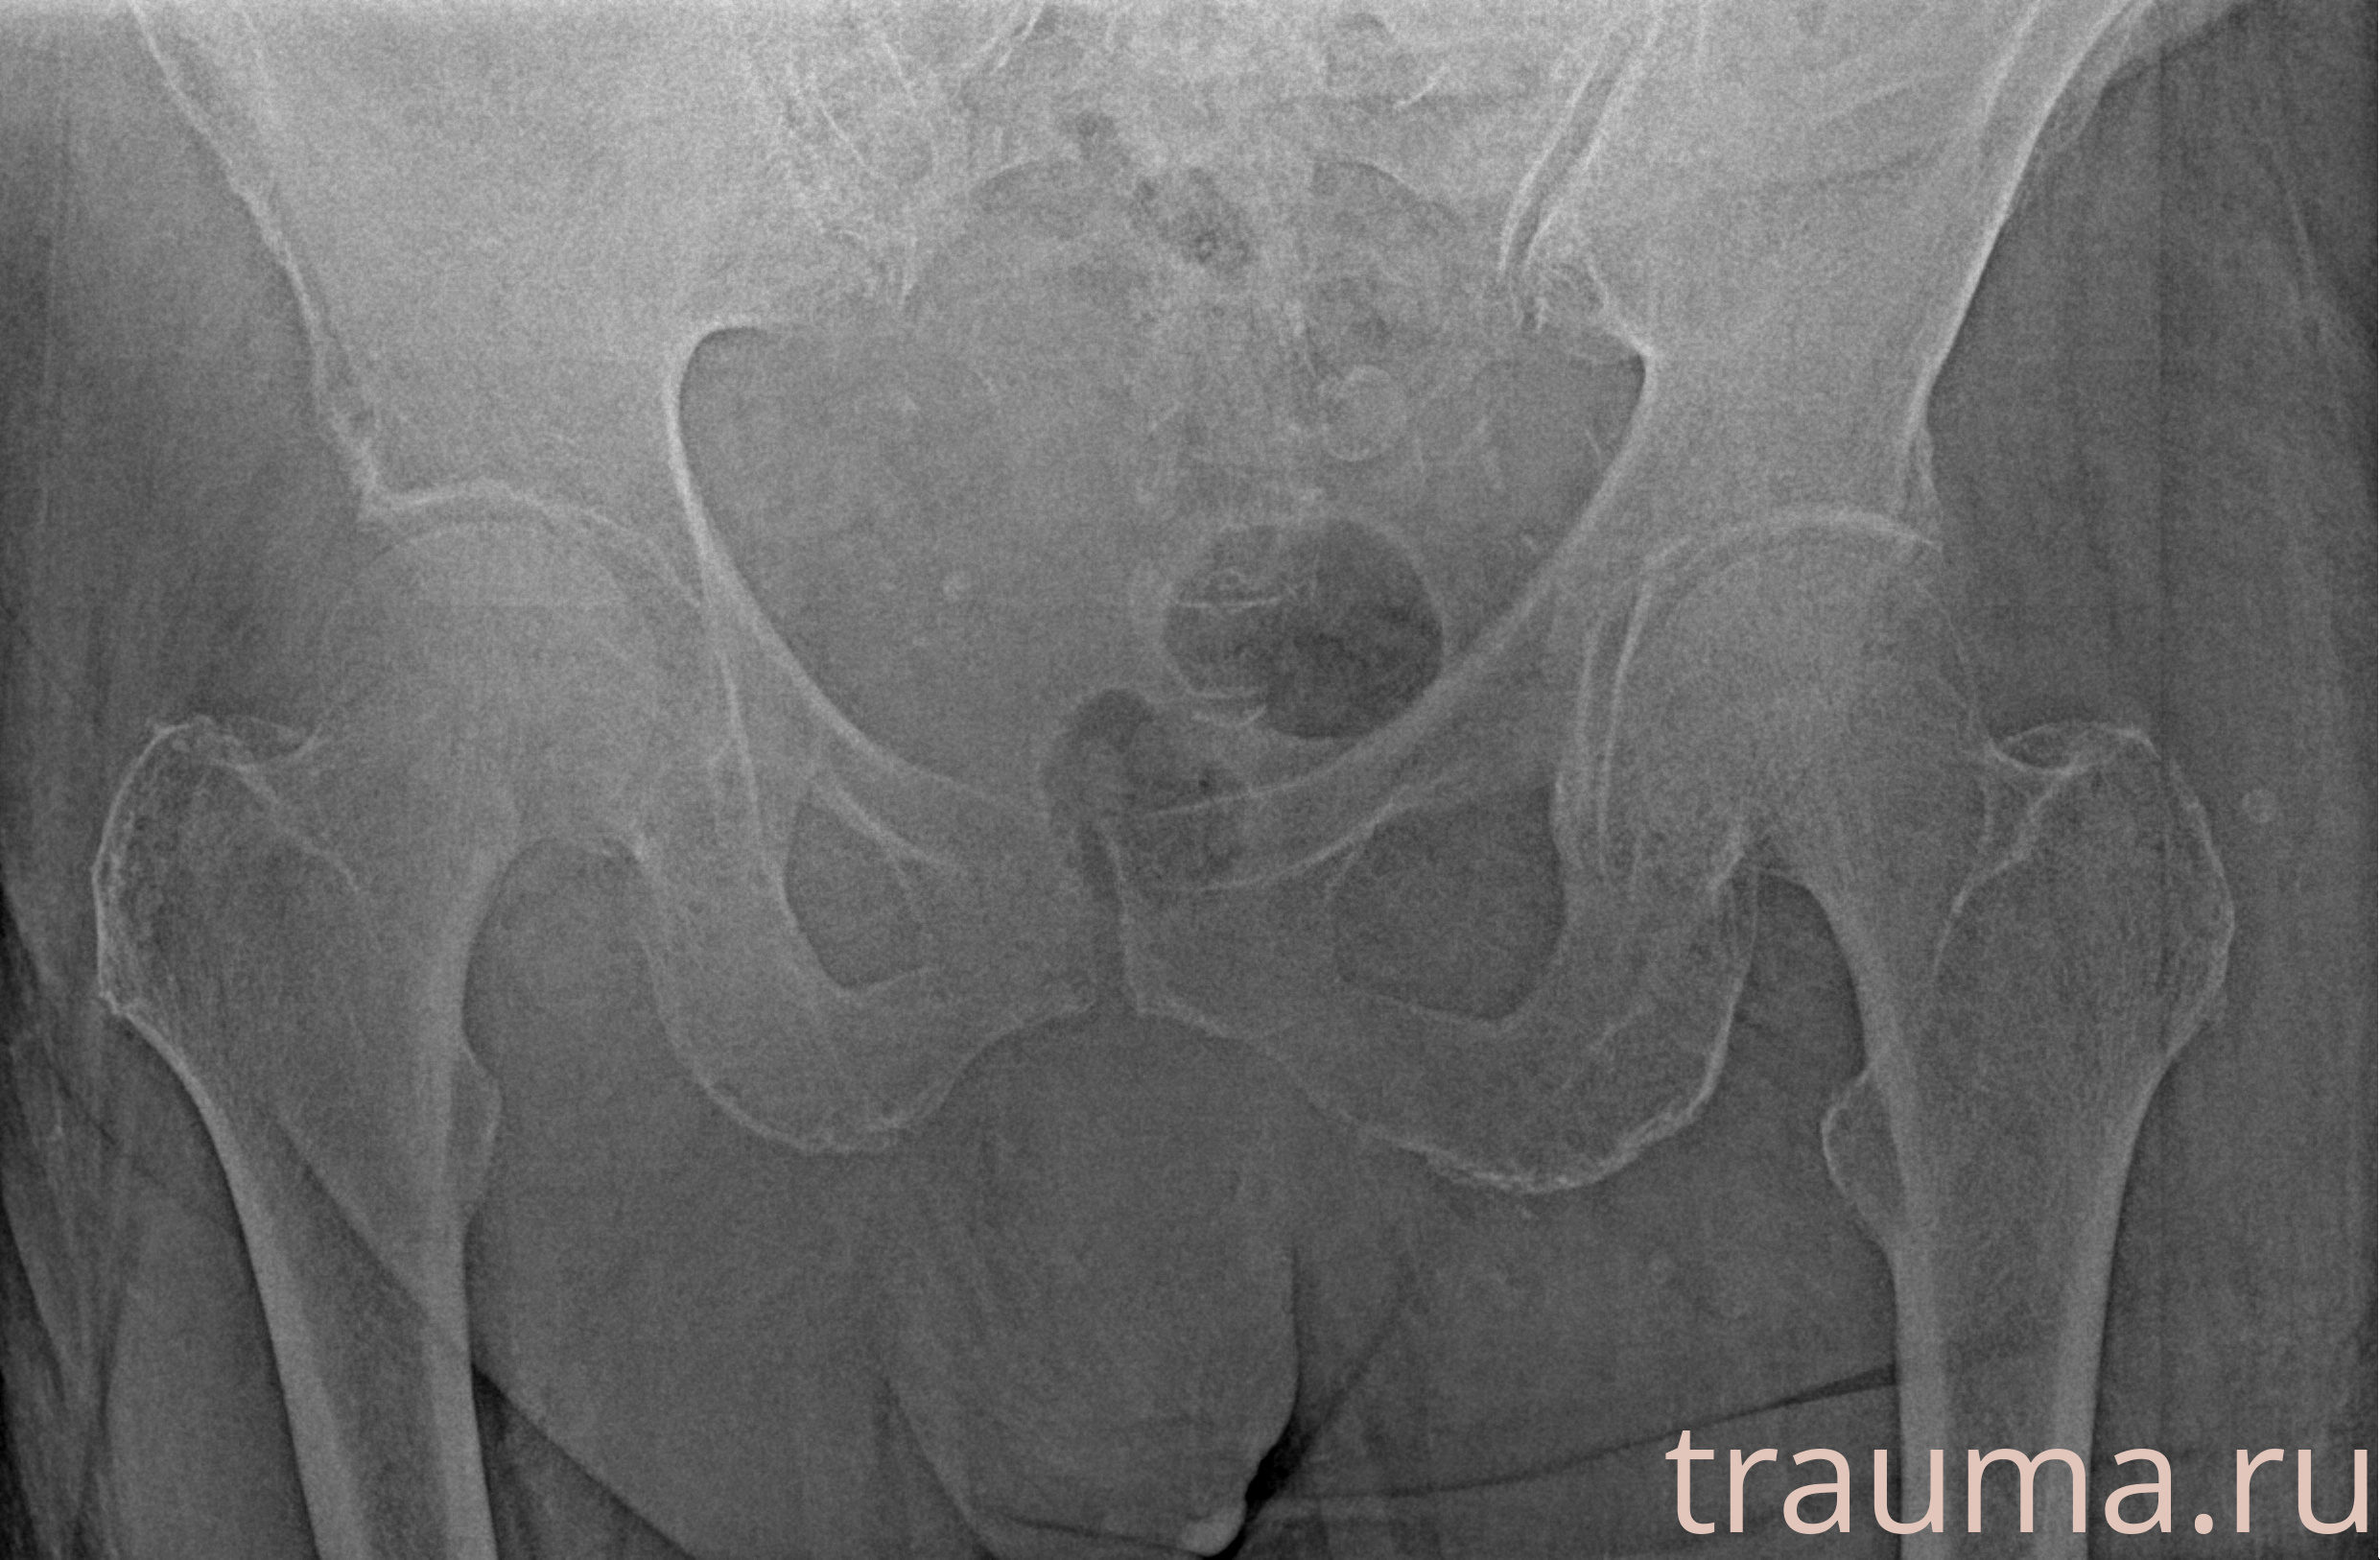

Рентгенограммы

Рентген на дому: по вашему адресу приезжает врач-рентгенолог, травматолог-ортопед с мобильным рентгеновским аппаратом, проводит диагностику травмы или заболевания, делает необходимые рентгенограммы, дает рекомендации по дальнейшему лечению. Получить качественные снимки в домашних условиях возможно благодаря уникальной методике, разработанной МосРентген Центром для института  Склифосовского